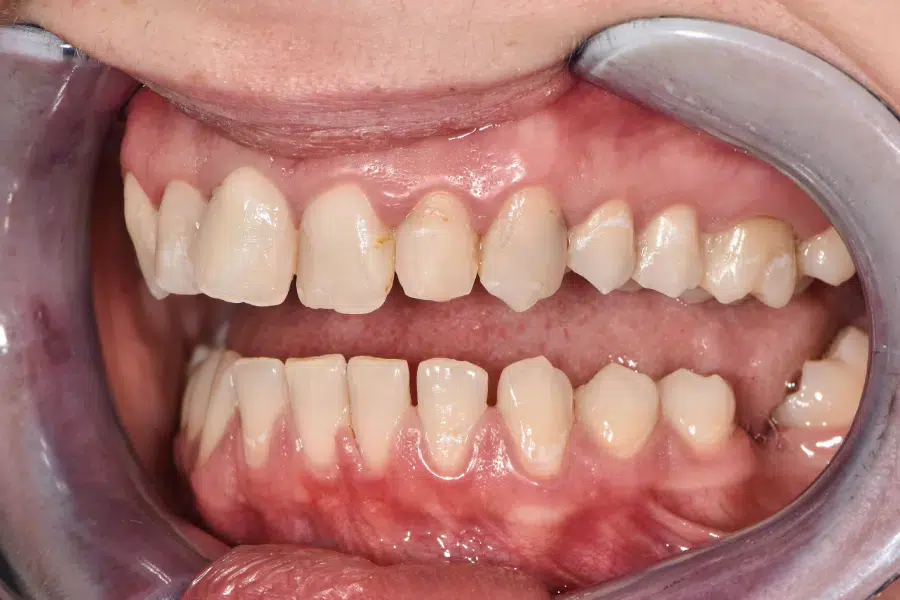

Caz de reabilitare totală orală.

Provocarea acestui caz a fost in reabilitarea totală a pacientului atâta a maxilarului superior cat și a mandibulei, tratând absolut toți dinții prezenți și reconstruindu-i cu pivoți de fibră de sticlă pentru a putea obține o susținere suficientă pentru viitoarele coroane.

Grupul superior fiind distrus complet, am efectuat tratamente la microscop, reconstrucția individuală a fiecărui dinte, tratamente parodontale cu laser pentru sănătatea ginigivala și am optat pentru coroane individuale de zirconiu ceramică pentru un plus de duritate și protecție a dinților cat și pentru o estetică frumoasă. Au fost folosite un set de provizorii de lungă durată pentru reechilibrarea articulației și muscaturii.

Pacientul a beneficiat inferior de igienizare în profunzime , detartraj și airflow, tratamente endodontice , obturații ( plombe) , tratamente parodontale cu laser iar în final punți și coroane individuale de zirconiu ceramica.

Termen de finalizare 2 săptămîni de la amprentarea finală.